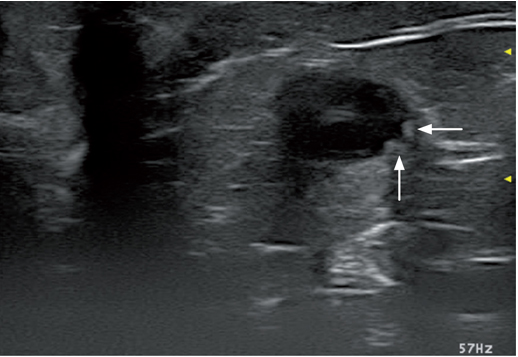

关于输尿管,沿着腹中腰肌走向,盆腔中端平面1-2cm 的侧面,靠近AO 和 CVC(见图.2); 输尿管穿过腹侧面的旋髂深血管和A0 及CVC 的终末分支。在骨盆的水平线上,输尿管沿阔韧带/或生殖器延伸一直到达膀胱三角区。膀胱和输尿管突起在同一水平线上。输尿管突起影像中可以看到是膀胱壁上的一个小团块。输尿管的喷射可以观察到反射波漩涡的图像,这个影像位于膀胱三角区至膀胱内腔的区域(图5.视频2)。健康猫输尿管的管腔直径是0.4 mm并且通过超声波很难观察到。有-点很重要:尿液是通过蠕动和收缩来流动的,因此只有当输尿管扩张的时候才能通过超声波观察。